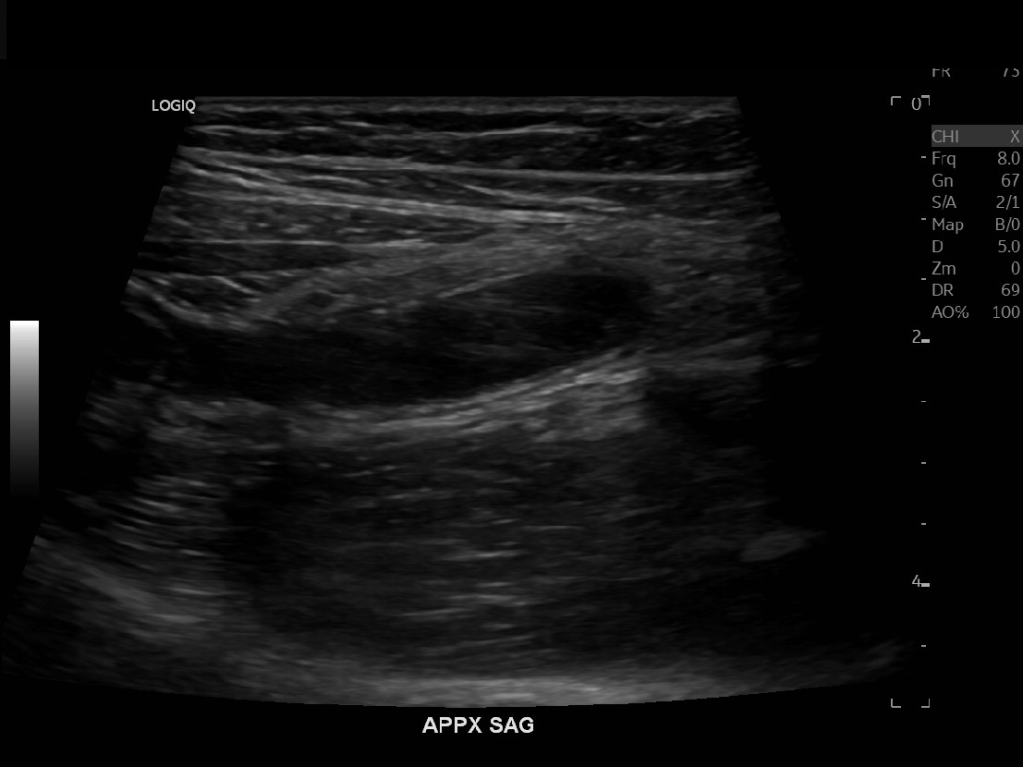

Appendicitis 13

Acute appendicitis @ 1 cm with L2-9mhz and L6-24mhz transducer GE Logiq e10.